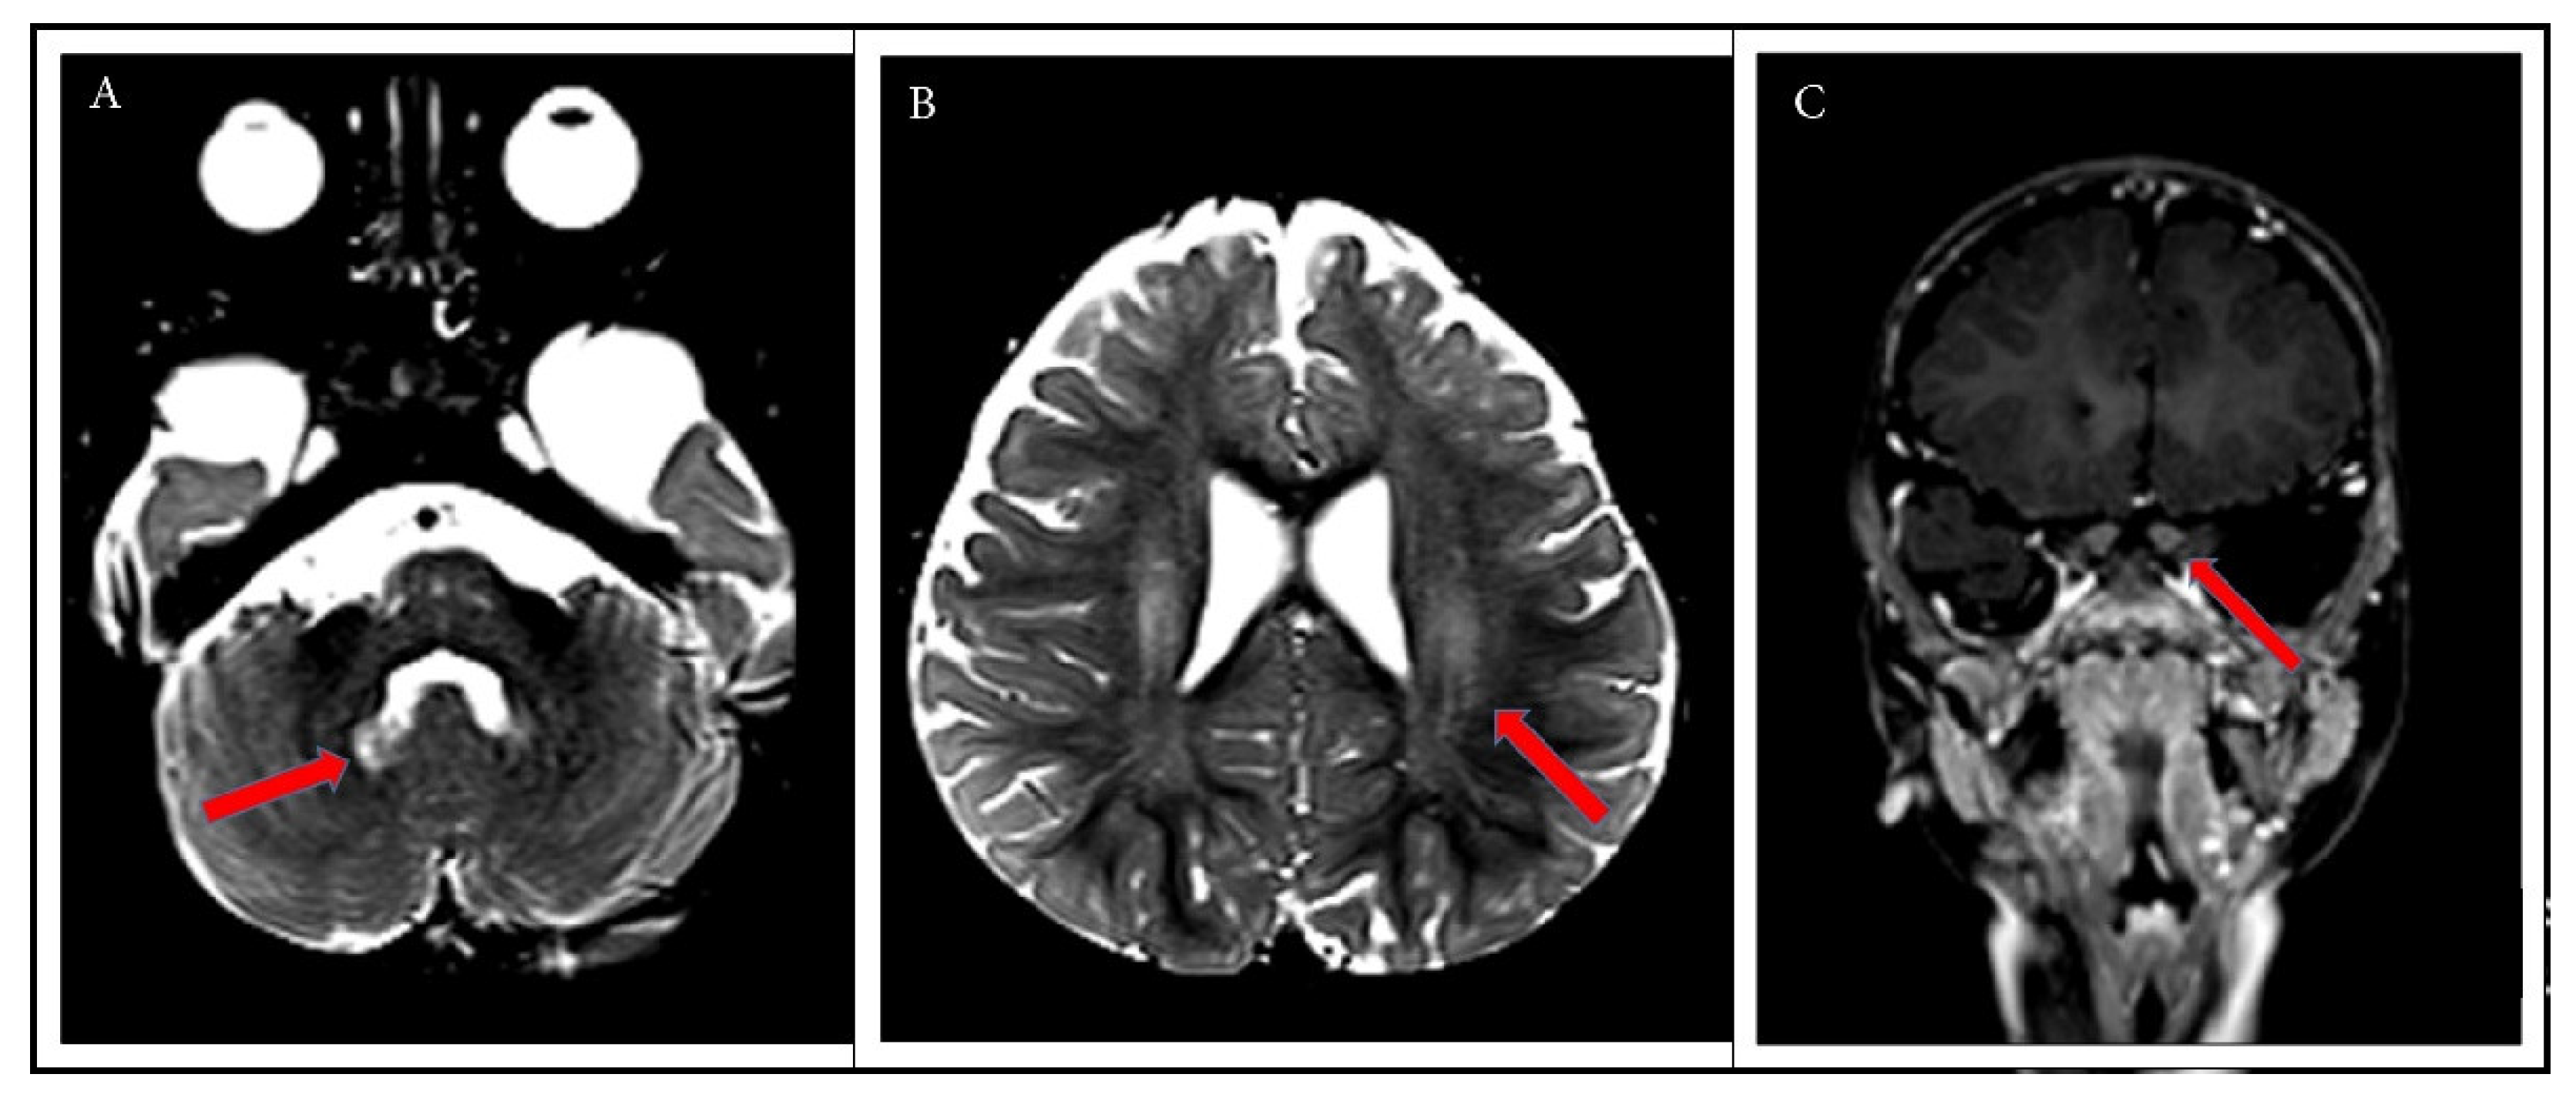

2. Case Report